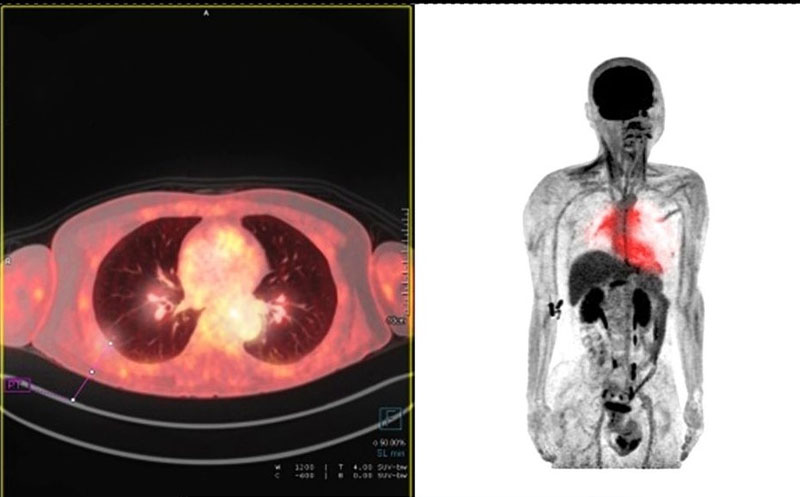

بسیاری از بیماران هنگام مشاهده تصاویر پت اسکن با سوالاتی مانند «نقاط قرمز در پت اسکن چیست؟» یا «آیا هر ناحیه قرمز نشانه سرطان است؟» مواجه میشوند. این نقاط رنگی معمولاً نشاندهنده افزایش مصرف ماده رادیواکتیو و فعالیت بالای سلولی هستند که میتواند به دلایل مختلفی از جمله تومورهای سرطانی، التهاب یا عفونت ایجاد شود. به همین دلیل، تفسیر دقیق عکس پت اسکن سرطانی نیازمند بررسی تخصصی توسط پزشک متخصص پزشکی هستهای است.

در عکس پت اسکن سرطانی (مثلاً تصویر یک PET/CT از تومور) ابتدا مهم است بدانید این تصاویر معمولاً به صورت رنگی با شدت نور متفاوت نمایش داده میشوند که فعالیت متابولیک غیرطبیعی (مثل سلولهای سرطانی) را نشان میدهند.

ویژگیهای عکس پت اسکن سرطانی:

- نقاط روشن (زرد، نارنجی، قرمز) نشان دهنده فعالیت متابولیک بالا و معمولاً نشان دهنده ناحیه سرطانی.

- نواحی تیره یا آبی نشاندهنده فعالیت کم یا بافتهای نرمال.

- اغلب با CT ترکیب میشود (PET/CT) تا محل دقیق ضایعه مشخص باشد

نقاط قرمز در پت اسکن چیست

نقاط قرمز در پت اسکن نشاندهنده نواحی از بدن هستند که در آنها جذب ماده رادیواکتیو بیش از حد طبیعی انجام شده است. در تصویربرداری PET Scan معمولاً از مادهای مانند FDG استفاده میشود که سلولهای فعالتر آن را بیشتر جذب میکنند. به همین دلیل، این نواحی در تصویر بهصورت نقاط قرمز، نارنجی یا زرد دیده میشوند.

در بسیاری از موارد، نقاط قرمز در پت اسکن میتوانند نشانه افزایش فعالیت متابولیکی سلولها باشند؛ حالتی که اغلب در سلولهای سرطانی مشاهده میشود. سلولهای سرطانی به دلیل رشد سریع، مصرف انرژی بالاتری دارند و همین موضوع باعث روشنتر دیده شدن آنها در تصویر پت اسکن میشود. با این حال، مشاهده نقاط قرمز همیشه به معنای سرطان نیست.

نکته مهم این است که برخی از اندامهای بدن مانند مغز، قلب، کلیهها و مثانه بهطور طبیعی جذب بالایی دارند و وجود نقاط قرمز در این نواحی کاملاً طبیعی است. همچنین عواملی مانند التهاب، عفونت، فعالیت عضلانی، یا حتی زمان نزدیک به جراحی میتوانند باعث ایجاد نقاط قرمز در پت اسکن شوند. به همین دلیل، تفسیر نقاط قرمز در پت اسکن باید همراه با بررسی محل، شدت جذب (SUV) و شرایط بالینی بیمار انجام شود.